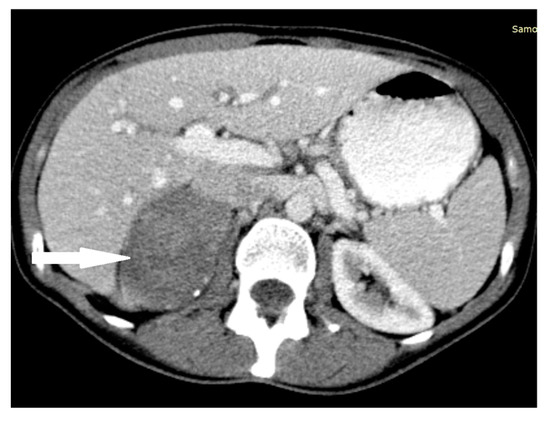

2.1. Case 1

2.2. Case 2

2.3. Case 3

2.4. Case 4

2.5. Case 5

2.6. Case 6

2.7. Case 7